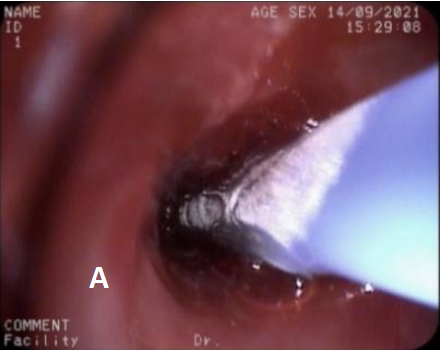

图4 第2次治疗(冷冻治疗+球囊扩张2021/9/14)

A. 冷冻治疗 B. 球囊扩张